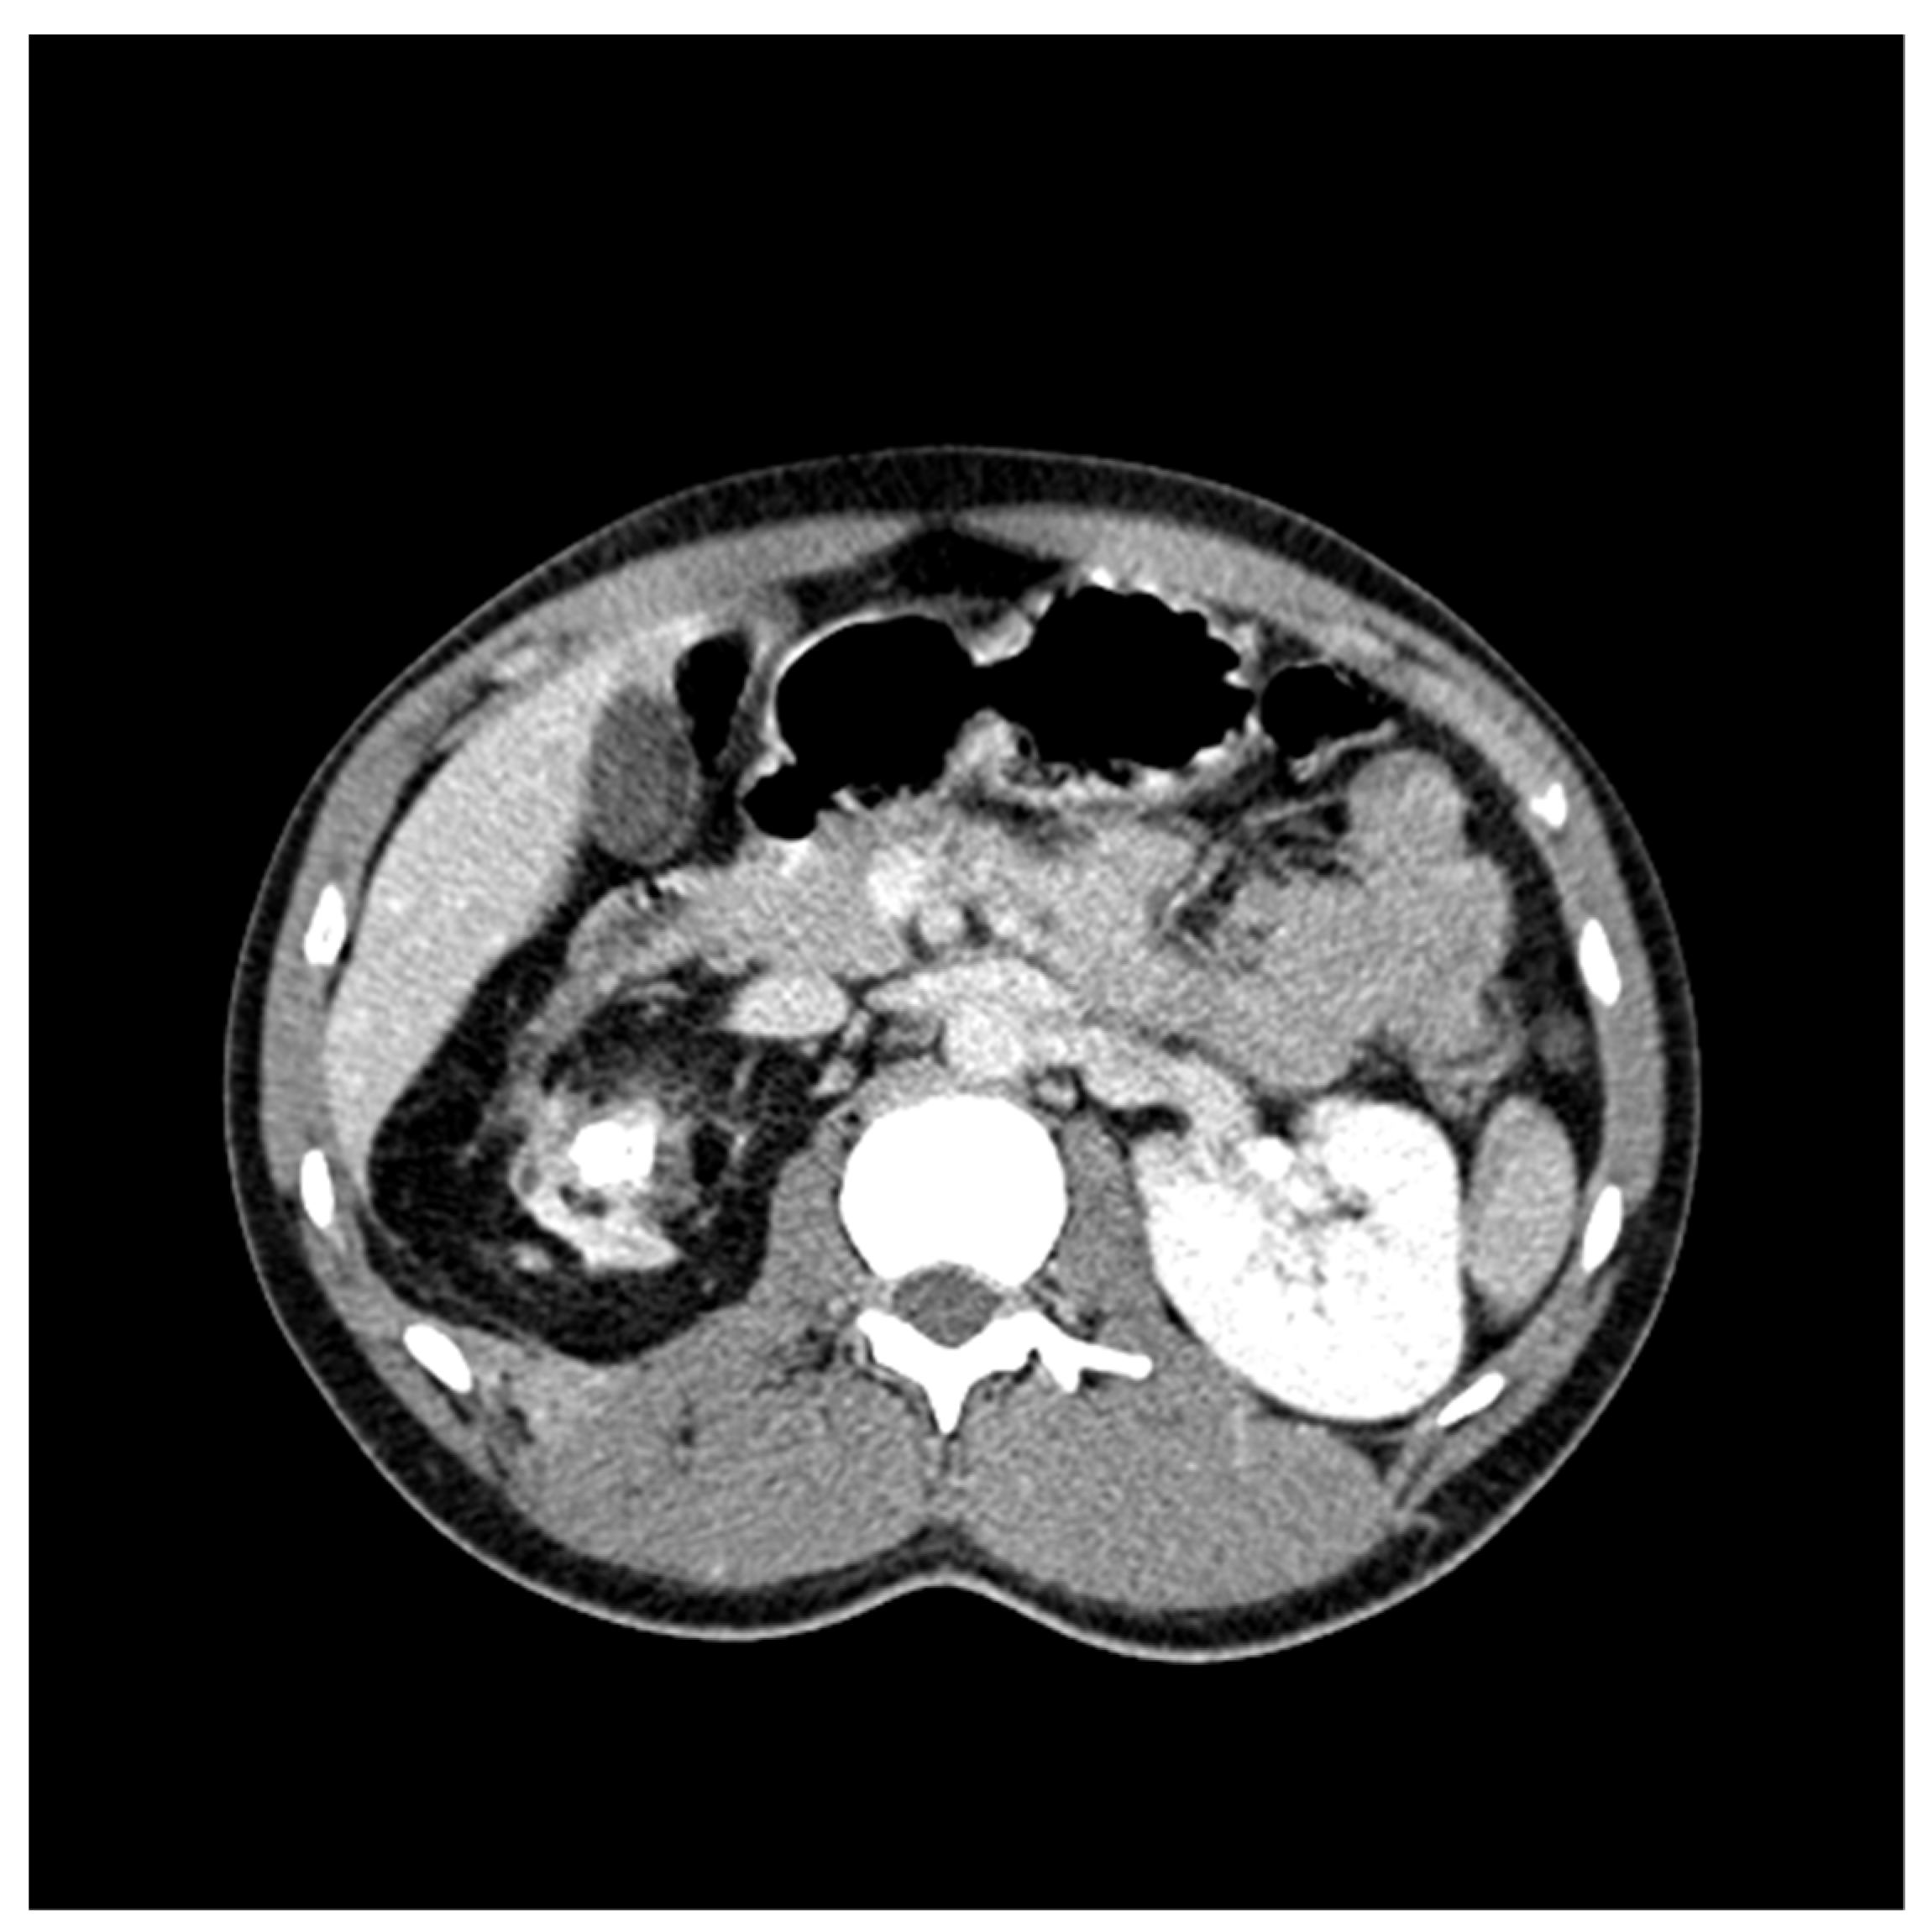

CT Scan and CT Urography

- Wang, L.-J.; Wu, C.-F.; Wong, Y.-C.; Chuang, C.K.; Chu, S.-H.; Chen, C.-J. Imaging findings of urinary tuberculosis on excretory urography and computerized tomography. J. Urol. 2003, 169, 524–528. [Google Scholar] [CrossRef]